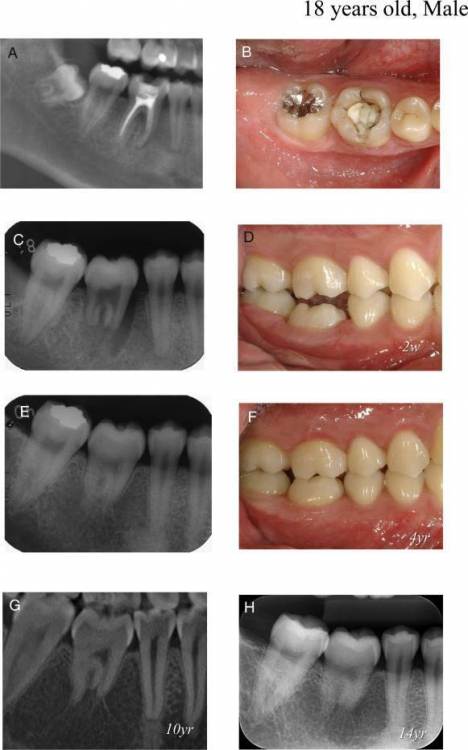

Dr.Deletle Опубликовано 22 июля, 2023 Поделиться Опубликовано 22 июля, 2023 (изменено) Этот кейс интересен тем, что у пересаживаемого 2.8 полностью сформированы корни. Пациент Н., 35лет, зуб 3.6 подлежит удалению по терапевтическим показаниям. Донором был выбран зуб 2.8. Фото №1, 2 - ситуация ДО на фото и срезе КЛКТ Фото №3 - планирование на реконструкции ОПТГ из КЛКТ Фото №4 - шаблон зуба 2.8 Фото №5, 6 - операция, удален 3.6, припасован шаблон, пересажен 2.8 (фиксирован швами и шиной к 3.7) Фото №7 - КТ сразу после пересадки Фото №8, 9 - депульпирование пересаженного 2.8 через 2 недели Фото №10 - снятие шины через 2нед после пересадки Фото № 11, 12, 13 - состояние в полости рта и на срезе КТ через год после пересадки, видно сформированное периодонтальное пространство, здоровая костная ткань, жалоб у пациента нет, полноценно жует как обычным зубом Изменено 22 июля, 2023 пользователем Dr.Deletle 4 3 Ссылка на комментарий

АнтонТЛТ Опубликовано 23 июля, 2023 Поделиться Опубликовано 23 июля, 2023 2 часа назад, annda сказал: Как на связку пульпа влияет ,не понимаю:( Если делаем аутотрансплантацию взрослому,эндо в любом случае делаем,тут нет вариантов.Или я чего-то не знаю? Если апекс не сформирован, то возможно пульпа может оживится при трансплантации 1 Ссылка на комментарий

Irouil Опубликовано 24 июля, 2023 Поделиться Опубликовано 24 июля, 2023 (изменено) Да, при незакрытой верхушке можно без эндо, хотя я ещё такие зубы не пересаживал, честно говоря Изменено 24 июля, 2023 пользователем Irouil Ссылка на комментарий